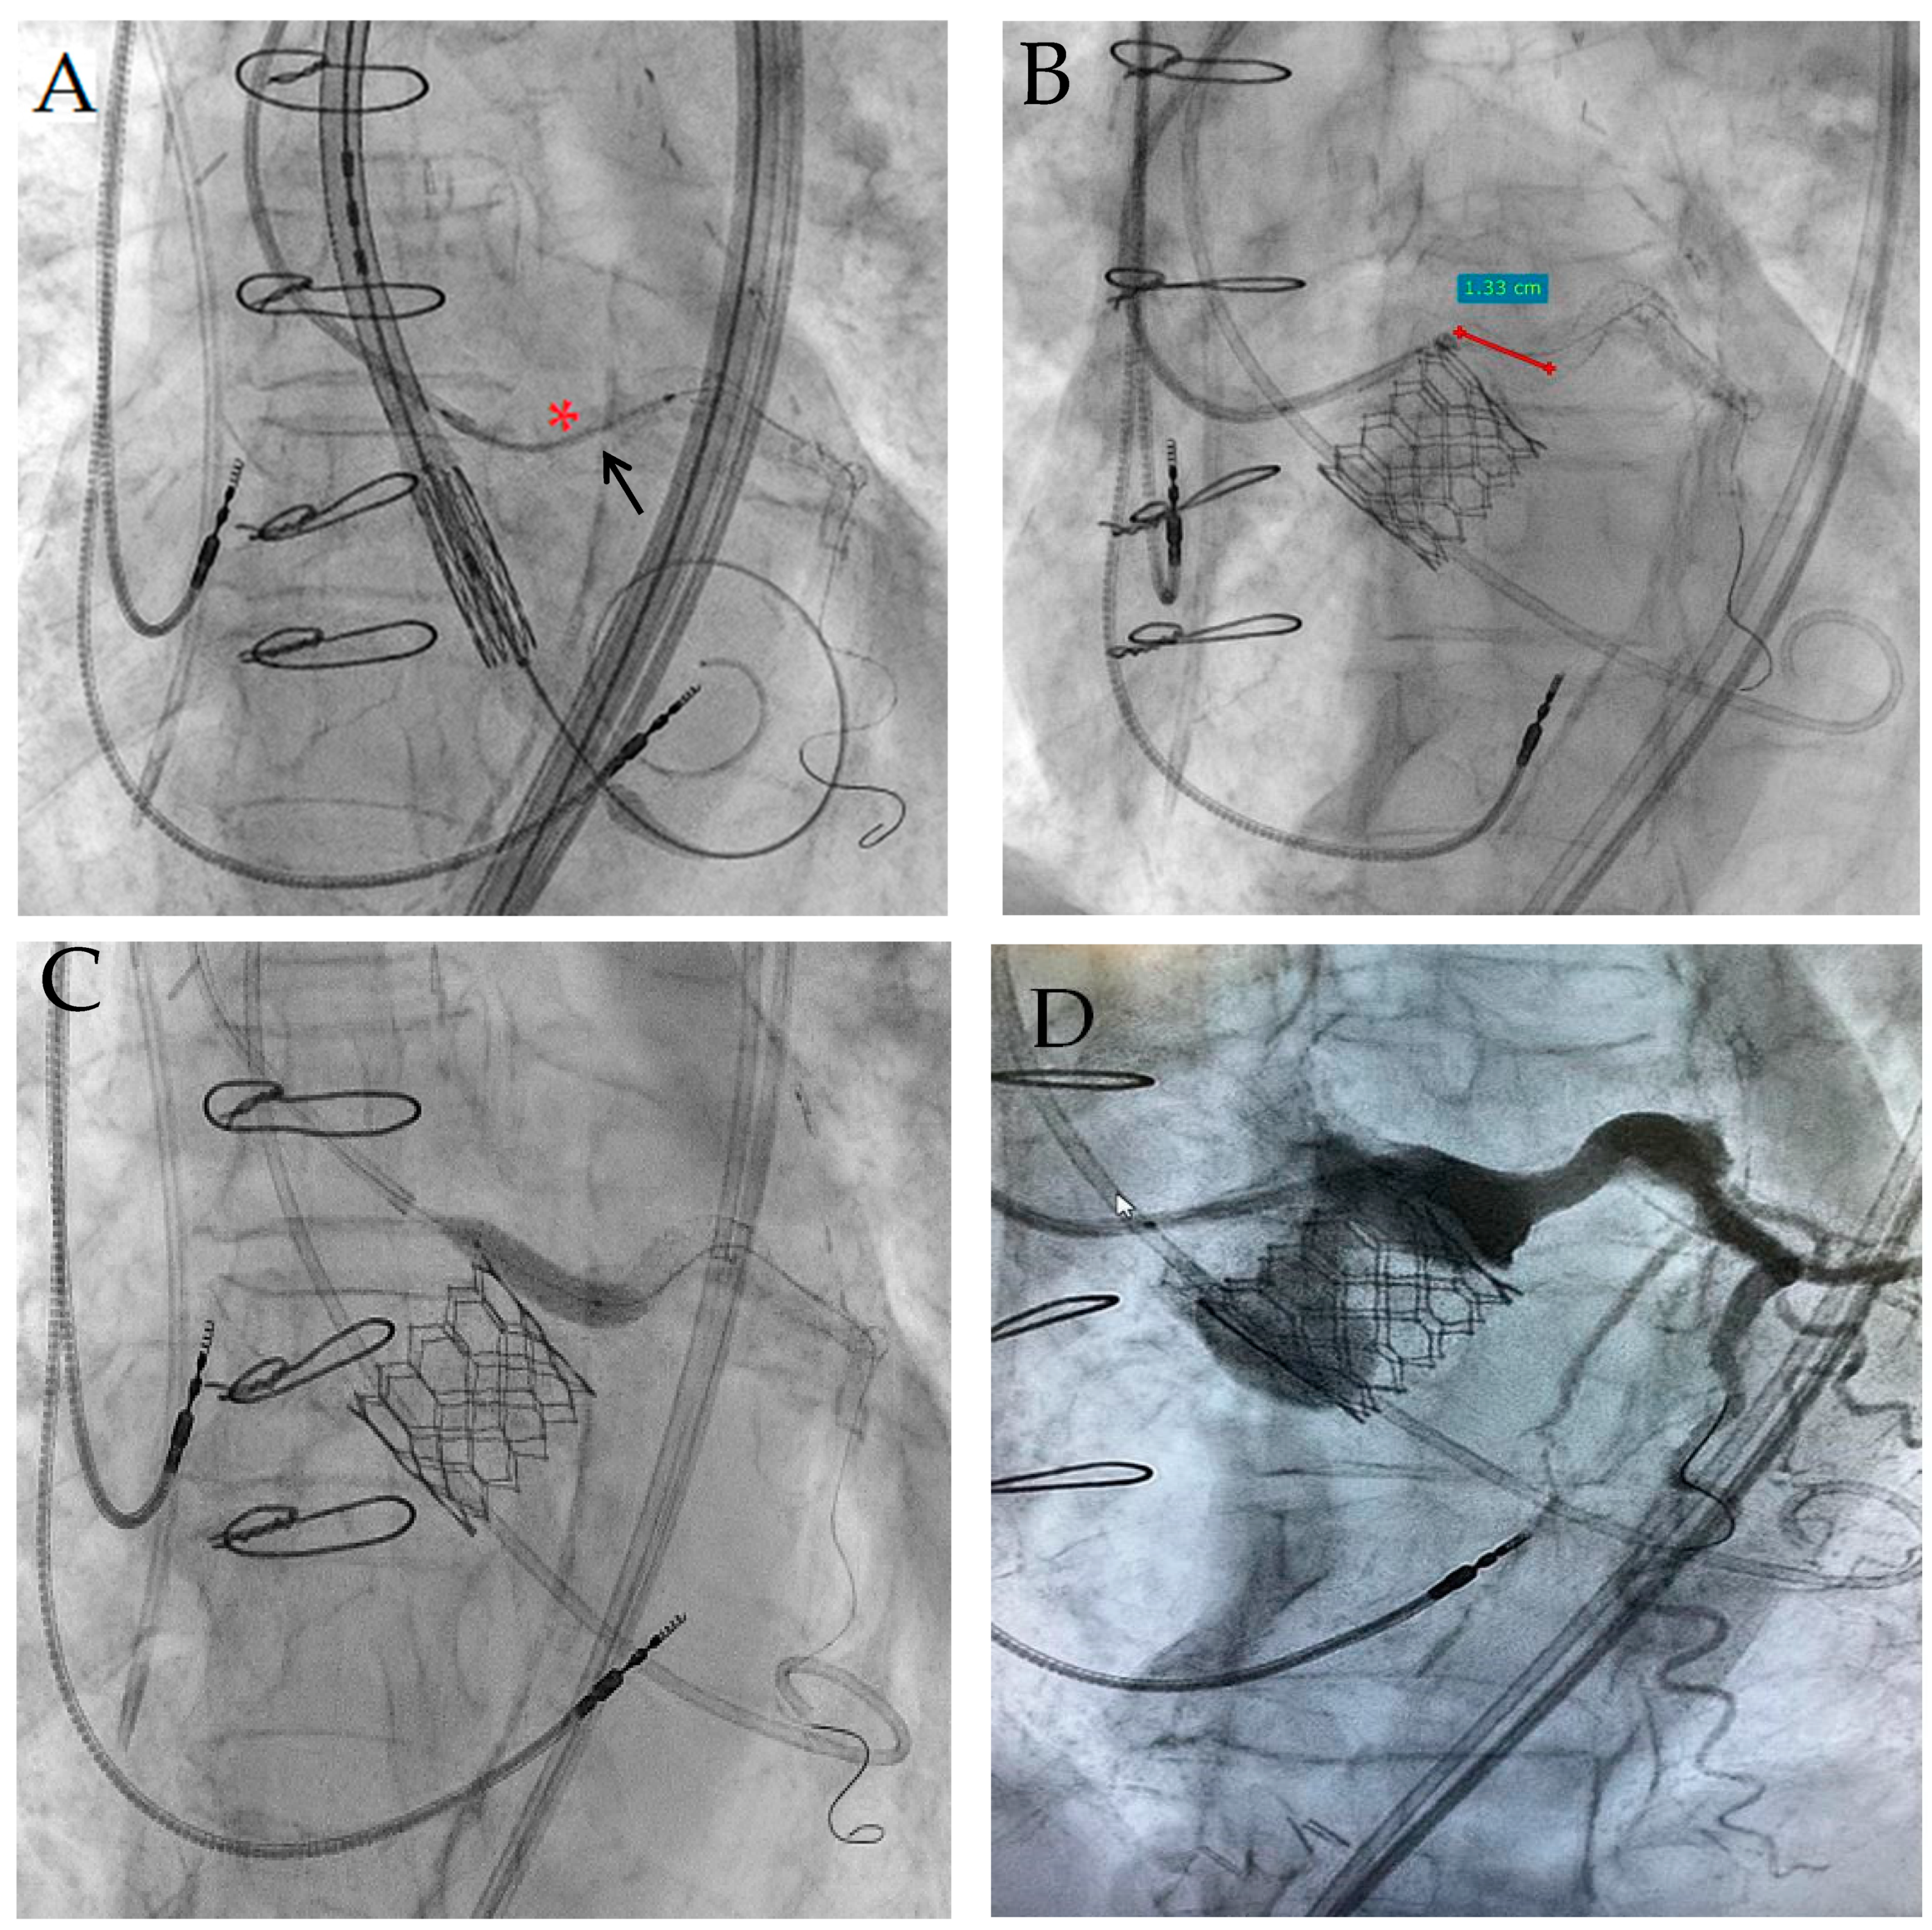

RLE-TRVP through the 0.035″ wire resulted unsuccessful because of unstable and inconstant stimulation. IC-TRVP was then successfully obtained in the same way as that described in Case 1; there were no significant issues on coronary vessels. After the pacing test, a self-expanding Evolut R™ (Medtronic, Minneapolis, MN, USA) 23 mm bioprosthesis was directly implanted with no significant paravalvular leak and a mean transvalvular gradient of 20 mmHg. After valve deployment, the “chimney stent” was promptly implanted (Figure 4A) and properly postdilated with a 4.5 mm non-compliant balloon, because of significant LMCA flow obstruction due to Direct Flow leaflet dislocation (asterisk in Figure 4B): the stent protrusion into the aorta was about 15 mm (Figure 4C). The “stent recrossing test” with 0.014″ guidewire was successful.

Figure 4. LMCA stent implantation (A); subselective coronary angiography after stent implantation with Direct Flow leaflet (asterisk) near LMCA ostium after Evolut R release (B); stent protrusion into the aorta (C).